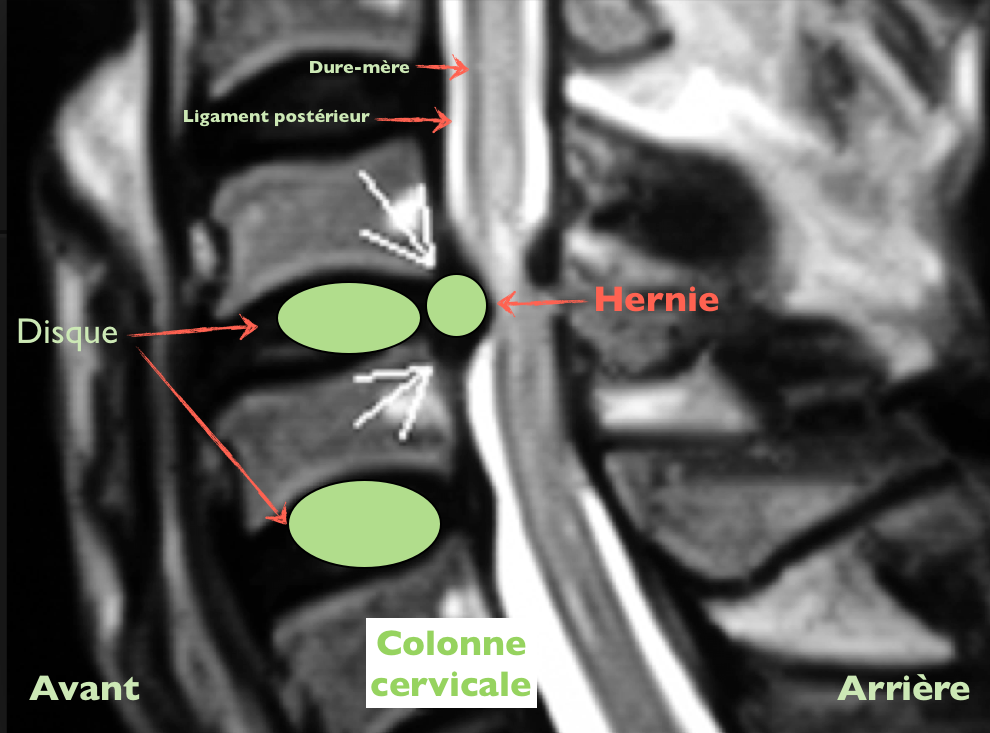

Parce que les disques peuvent « irriter » des structures anatomiques proches…

Cette personne souffre sûrement

Dans tout (ou une partie) de ces zones en rouge

Car le ligament postérieur et la dure-mère (dernière enveloppe de la moelle) sont très innervés (très sensibles)